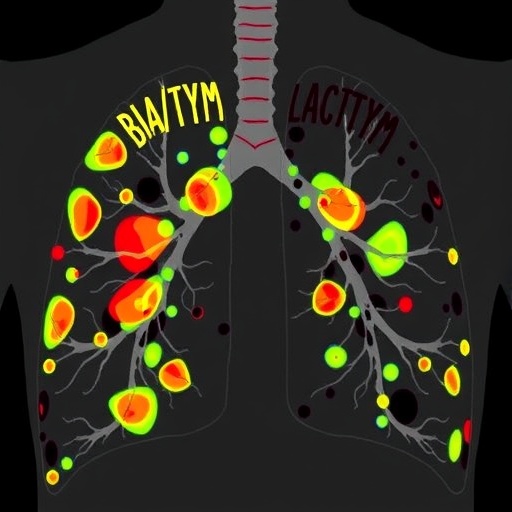

The intricacies of lymph node involvement in lung cancer are of paramount importance to clinicians and researchers alike. Identifying the lymph node metastasis atlas created in this study offers groundbreaking insights into how and where this cancer type commonly spreads. The atlas serves as a vital tool, as it underscores the specific lymphatic pathways often traversed by metastatic cells, thereby allowing surgeons to map out their approach to lymph node dissection more effectively.

Crucial to the authors’ methodology was the use of advanced imaging techniques and histopathological analysis. These modalities were instrumental in accurately identifying metastatic lymph nodes and determining their status concerning the primary tumor. The strength of their investigative approach lies in its comprehensiveness; every aspect, from the preoperative imaging studies to postoperative histology, was meticulously documented, laying the groundwork for a thorough analysis.

Another significant aspect of this study is its focus on optimal lymph node dissection strategies. The findings suggest a tailored approach, emphasizing the need for personalized surgical interventions based on the individual metastatic patterns outlined in the lymph node metastasis atlas. This adaptability could lead to more refined surgical techniques that minimize morbidity while maximizing oncological clearance, thereby potentially improving overall survival rates.